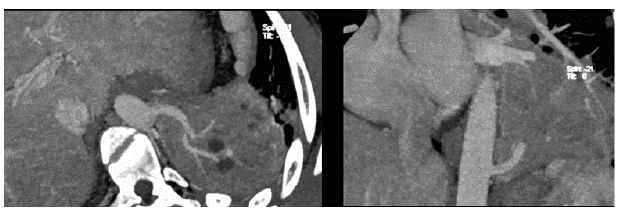

En la tomografía de tórax se observó una consolidación de todo el lóbulo inferior izquierdo con broncograma aéreo, además de un vaso arterial aberrante que emerge de la aorta torácica hacia el lóbulo inferior izquierdo, confirmándose la sospecha diagnóstica de secuestro pulmonar (figuras 5 y 6).

El paciente fue llevado a cirugía para una resección por videotoracoscopia, con la que se evidenció un lóbulo pulmonar hepatizado, irrigado por un gran vaso arterial, proveniente de la aorta torácica, lográndose completar la lobectomía inferior izquierda por videotoracoscopia, previa ligadura del vaso aberrante.